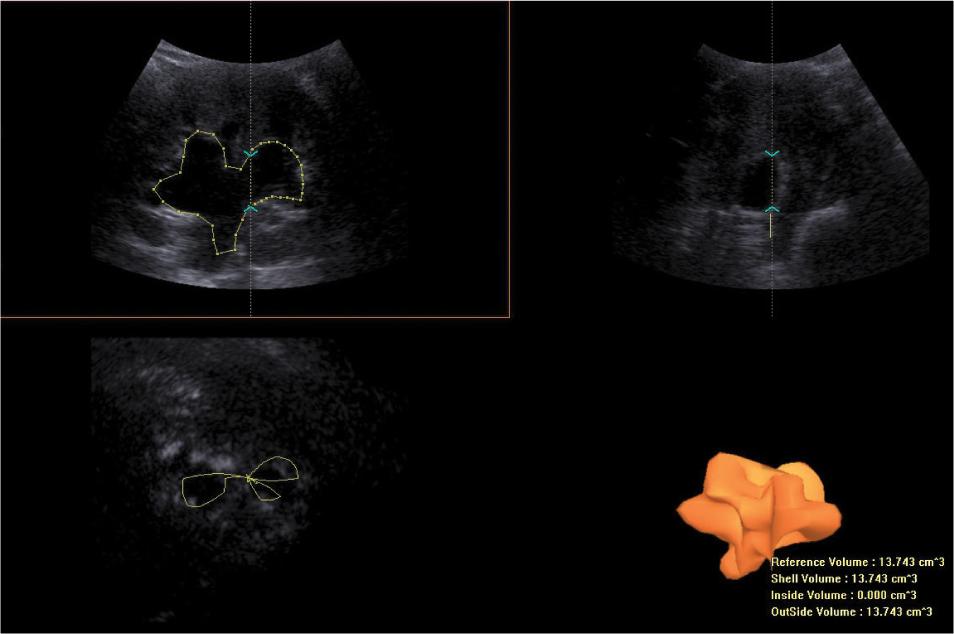

Fig. 5.

Three-dimensional ultrasound assessment of urine retention volume in the pelvicalyceal system. The VOCAL software has been used for volume calculations. Estimated pelvicalyceal volume = 13.74 cm3. The case presented in Fig. 2